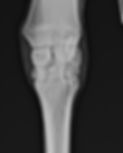

We have multiple portable state of the art Digital Radiograph machines. Capable of imaging necks, skulls, backs, and legs. We can radiograph horses on site, where they are most comfortable. We are able to instantly send those images to referring veterinarians. We have two plates, which allow for large areas like the

Diagnostic imaging often requires follow up scans and radiographs to monitor progression of healing.